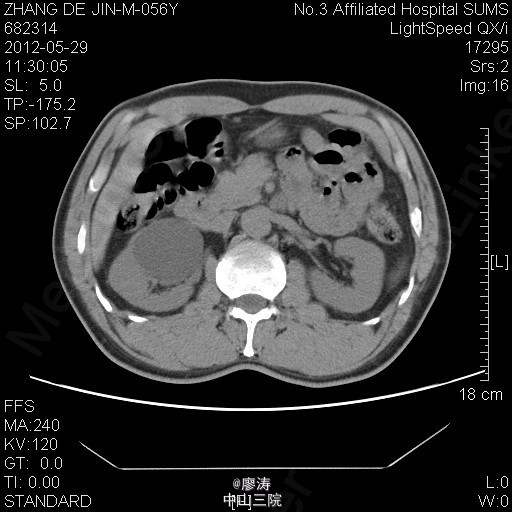

患者男,56岁,因腰痛2年到当地医院检查,当地医院彩超提示:右肾下部无回声区,考虑肾囊肿可能性大,右肾上盏局限性积液,余未见明显异常。为进一步治疗来我院就诊,行腹部CT检查提示右肾巨大囊肿,压迫右侧肾盂及中下盏。

腹部CT检查提示右肾巨大囊肿